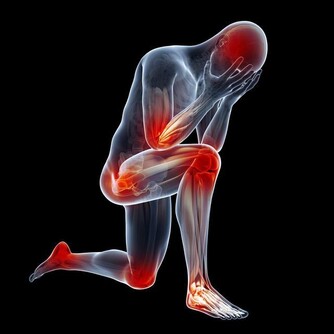

如果癌症擴散到前列腺外,會出現其他症狀。這些症狀包括:

1. 勃起困難;

2. 感覺很累,怎麼著都不舒服;

3. 骨頭或背部感覺疼痛;